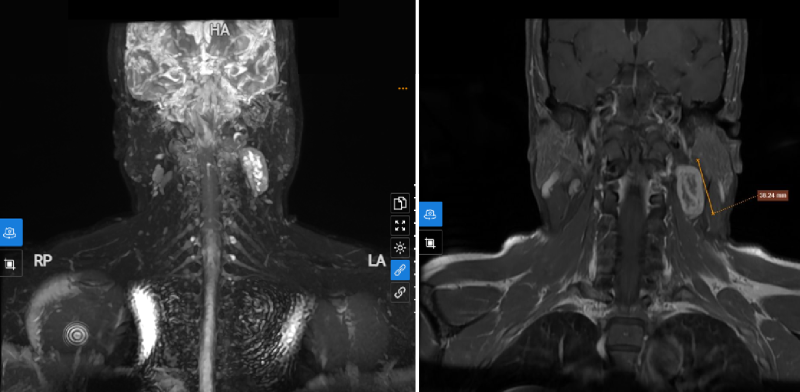

Hình ảnh đột quỵ thân não thường không thể hiện rõ qua chụp CT-Scanner hay MRI như đột quỵ xảy ra các vùng khác của não, có trường hợp không hề thấy tổn thương. Mặt khác, các phần trên cột sống và xương lân cận hộp sọ thường che khuất tổn thương ở thân não. Vì thế, để chẩn đoán đúng đột quỵ thân não đòi hỏi bác sĩ chuyên khoa phải có bề dày kinh nghiệm lâu năm và trình độ chuyên môn rất sâu.

Cơn đột quỵ thân não thường được chẩn đoán qua khám lâm sàng và chụp CT-Scanner hoặc chụp MRI nhưng cần theo dõi từ vài ngày đến vài tuần thì mới thấy được hình ảnh tổn thương.

Chụp MRI giúp tầm soát hiệu quả đột quỵ thân não

Tầm soát đột quỵ thân não bằng chụp MRI có thể phòng ngừa hiệu quả bệnh lý này. Đây là phương pháp được đánh giá cao nhất về độ phân giải hình ảnh hiện nay, cho phép phát hiện bất thường bị khuất lấp sau xương và không gây tác dụng phụ như việc sử dụng phương pháp chẩn đoán hình ảnh bằng tia X nên có thể an tâm về tính an toàn.